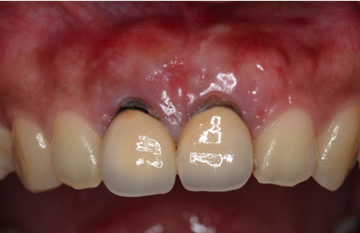

治療例 2

上顎左側1番の被せ物が外れてしまった事、同右側1番の被せ物と歯茎の間に隙間ができた事を主訴に来院。自然な見た目で強度もしっかりある被せ物を装着しました。